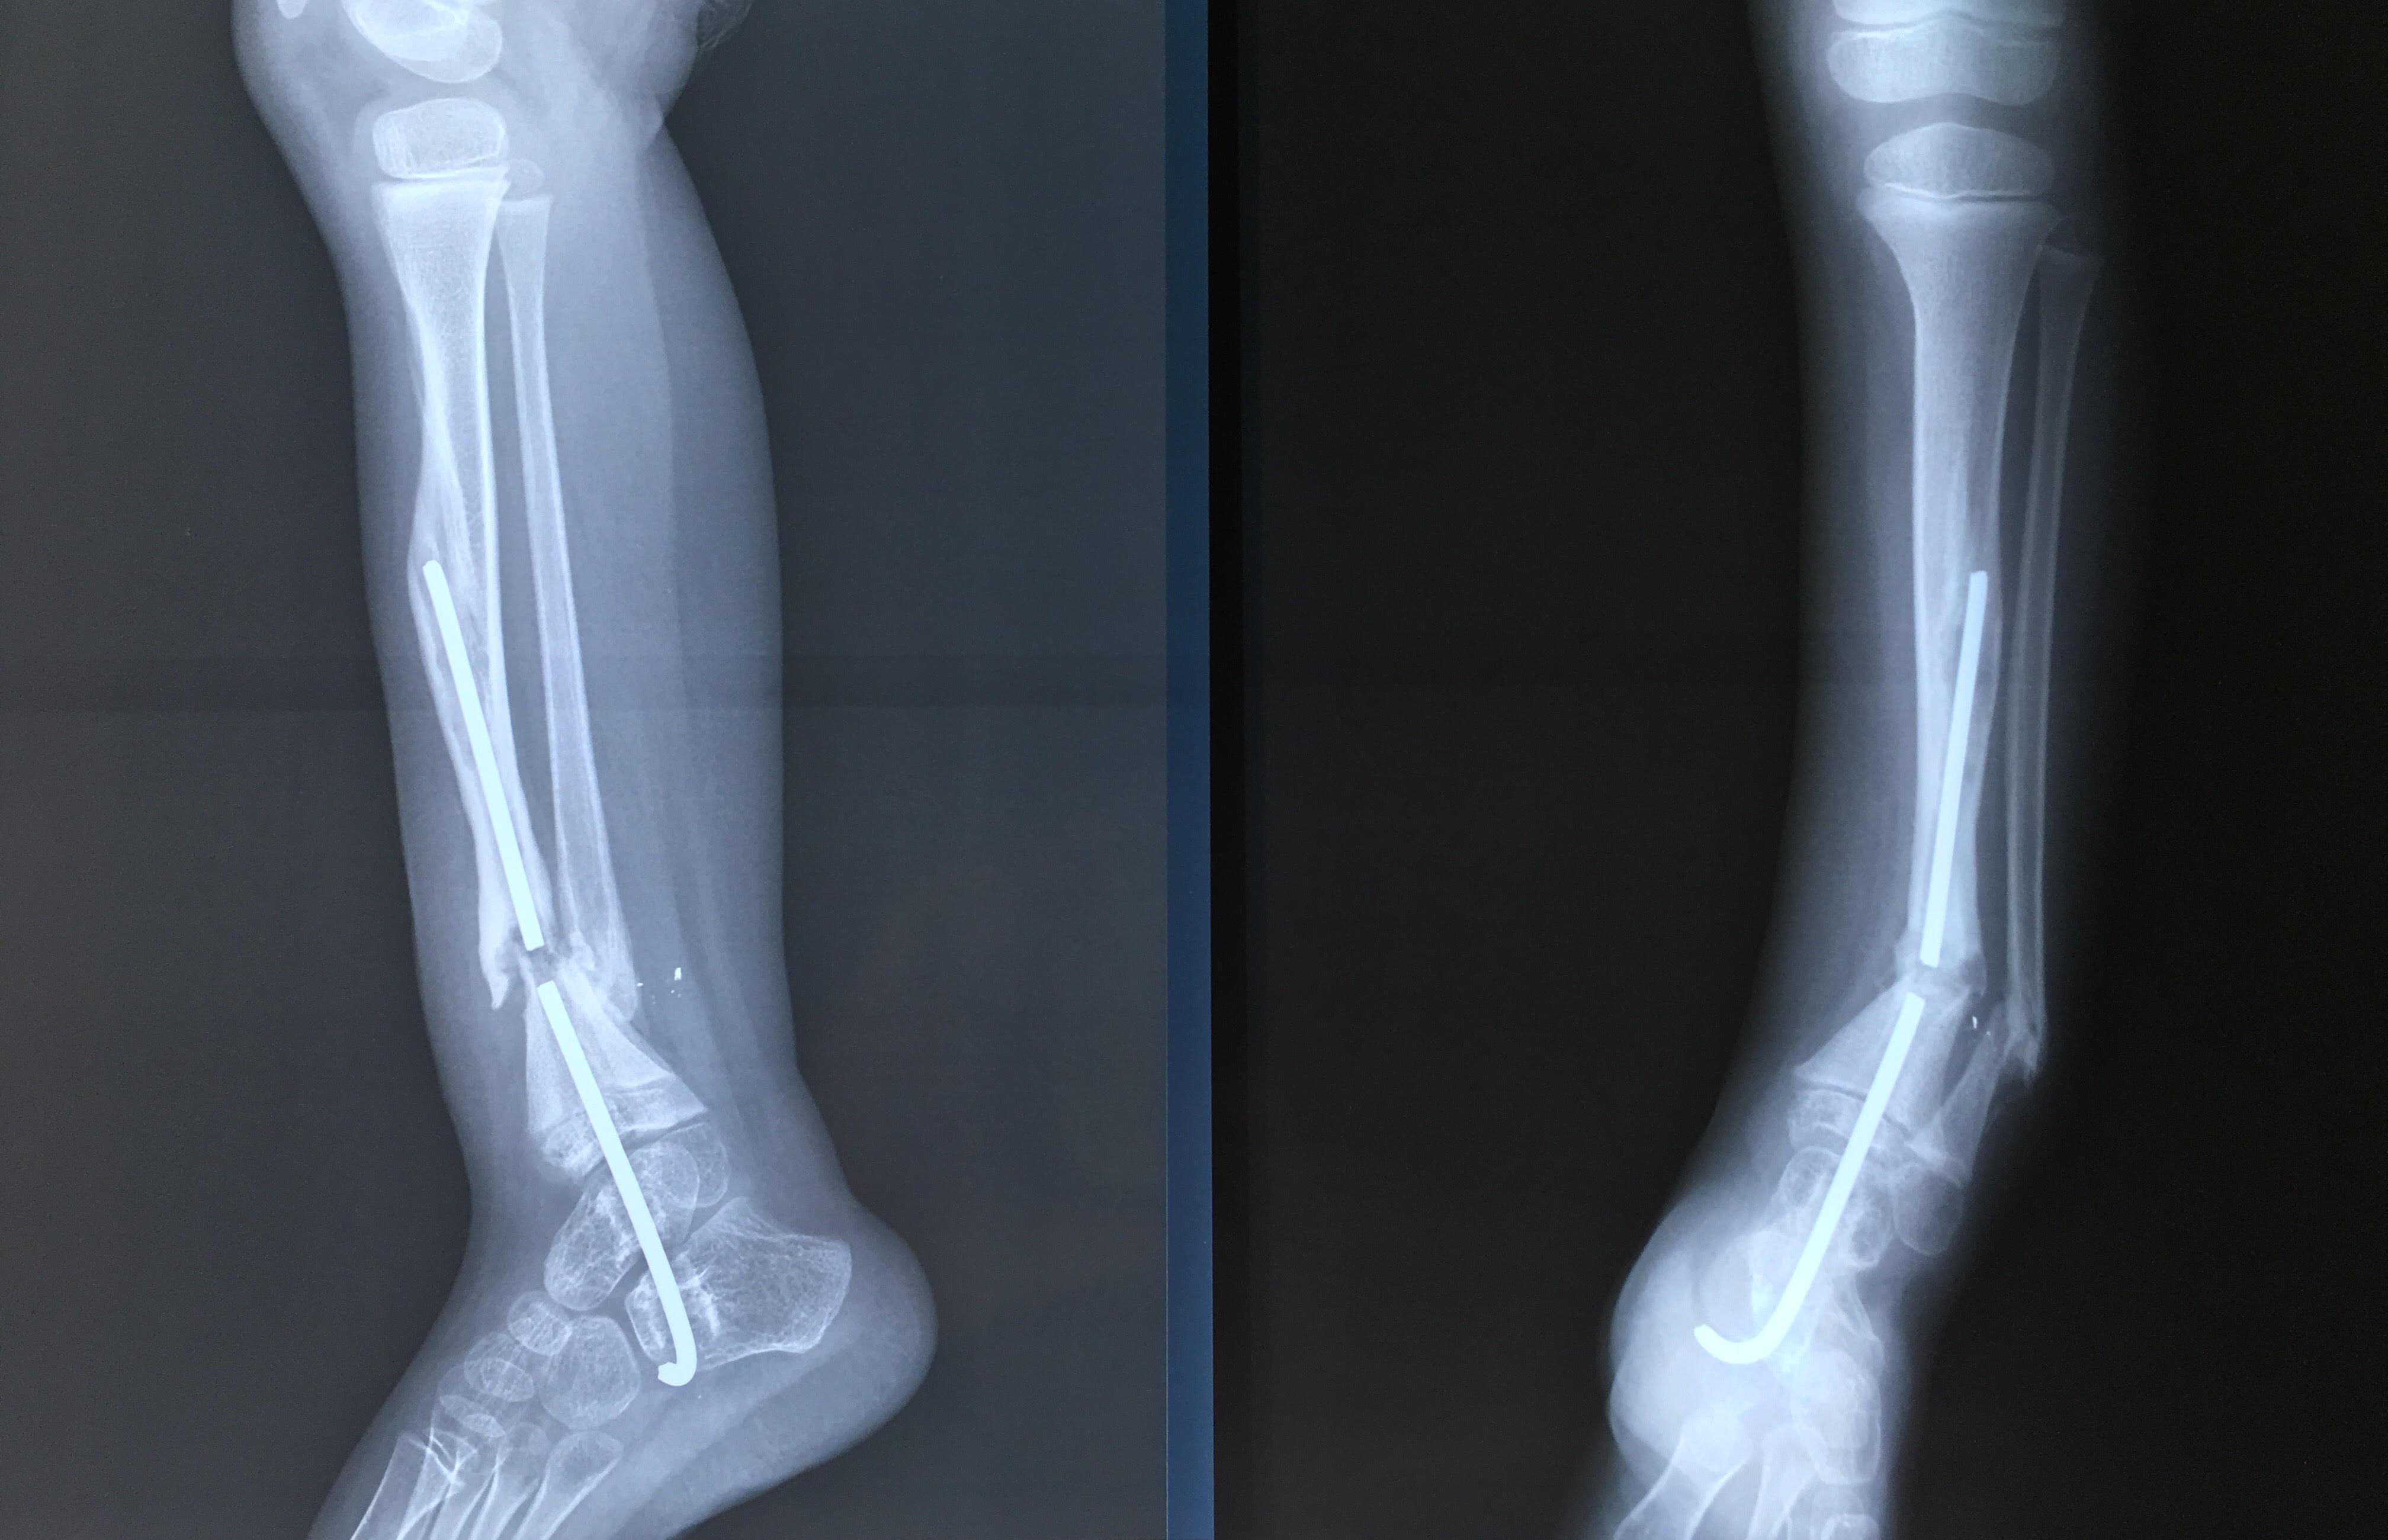

Phẫu thuật thành công ca bệnh hiếm gặp...khớp giả bẩm sinh xương chày

26/06/2019 17:00

Đã xem: 3705

Bệnh viện Chấn thương- Chỉnh hình Nghệ An, vừa phẫu thuật thành công cho bệnh nhi khớp giả bẩm sinh xương chày